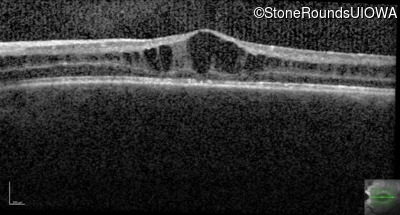

Age at visit: 11 years

This 11 year old male was never correctable to 20/20. He received glasses at age 1 for esotropia. His refraction is +4.25 +2.00 x 105 OD and +2.00 +2.00 x 80 OS.

Age at visit: 13 years

Age at visit: 15 years

Age at visit: 17 years

Age at visit: 18 years